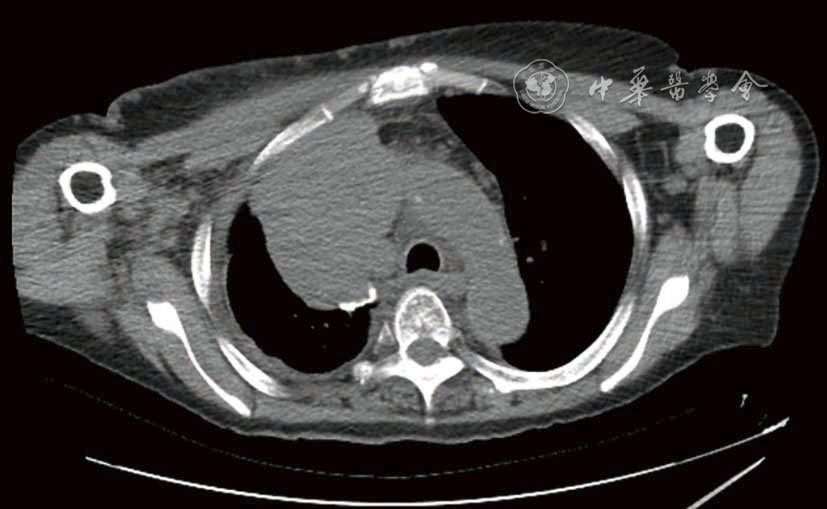

图1 治疗前CT影像 2023年6月29日,入院时胸部CT:右肺门旁可见不规则肿物影,最大横截面积约为8.5 cm×7.1 cm,其内可见类圆形低密度影及不规则致密影。